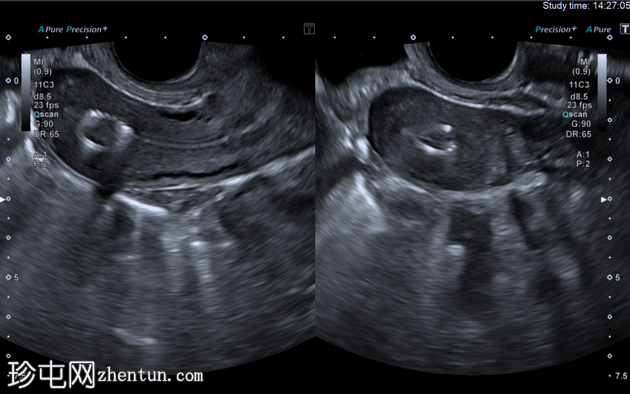

1.png

纵切面

纵切面和横切面经阴道超声图像显示子宫内膜腔内有一个高回声肿块,呈圆形,并具有典型的“珍珠串”样外观,符合宫内节育器(IUB)的特征。

在超声图像上,宫内节育器通常表现为子宫内膜腔内的高回声圆形结构,常呈现出由铜线圈产生的典型“珍珠串”样外观。在高分辨率经阴道超声检查中,纵切面和横切面均可清晰显示该特征。后方声影可能存在,但通常不如硬性宫内节育器(IUD)的后方声影明显。